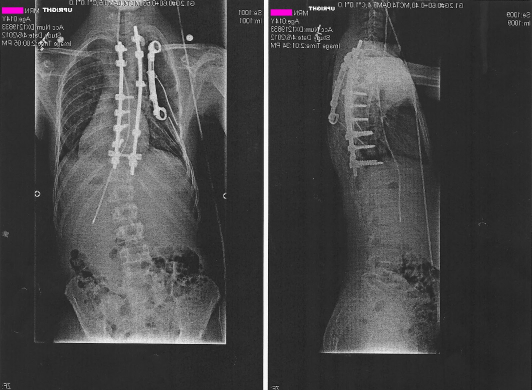

On June 25th 2007 I was diagnosed with Ewing's Sarcoma. This is a rare form of bone cancer typically only found in 10-20 year olds. This image is mirrored to reflect that the tumor was on the right side. You can click on any of the images for full images of the X-ray/Bone scan/CAT scan.

DeadSarcoma.png

For the next 4 months I was treated with # individual rounds of chemotherapy I was brought in for surgery to remove the tumor. This surgery removed 3 of my ribs, 4-6, from spine to armpit. These were replaced with a VEPTR, Vertical, Expandable, Prosthetic, Titanium, Rib. This prosthetic is clamped onto ribs 3 and 7 spanning the vertical gap. It also has titainum wires wrapped around and inserted into the remaining rib sections to emulate the ribs. Additionally a section of Gortex was added to strengthen the chest wall. Following this surgery I had another # chemotherapy treatments bringing the total up to 14 to total rounds. On March 1st 2008 I finished my last chemo treatment.